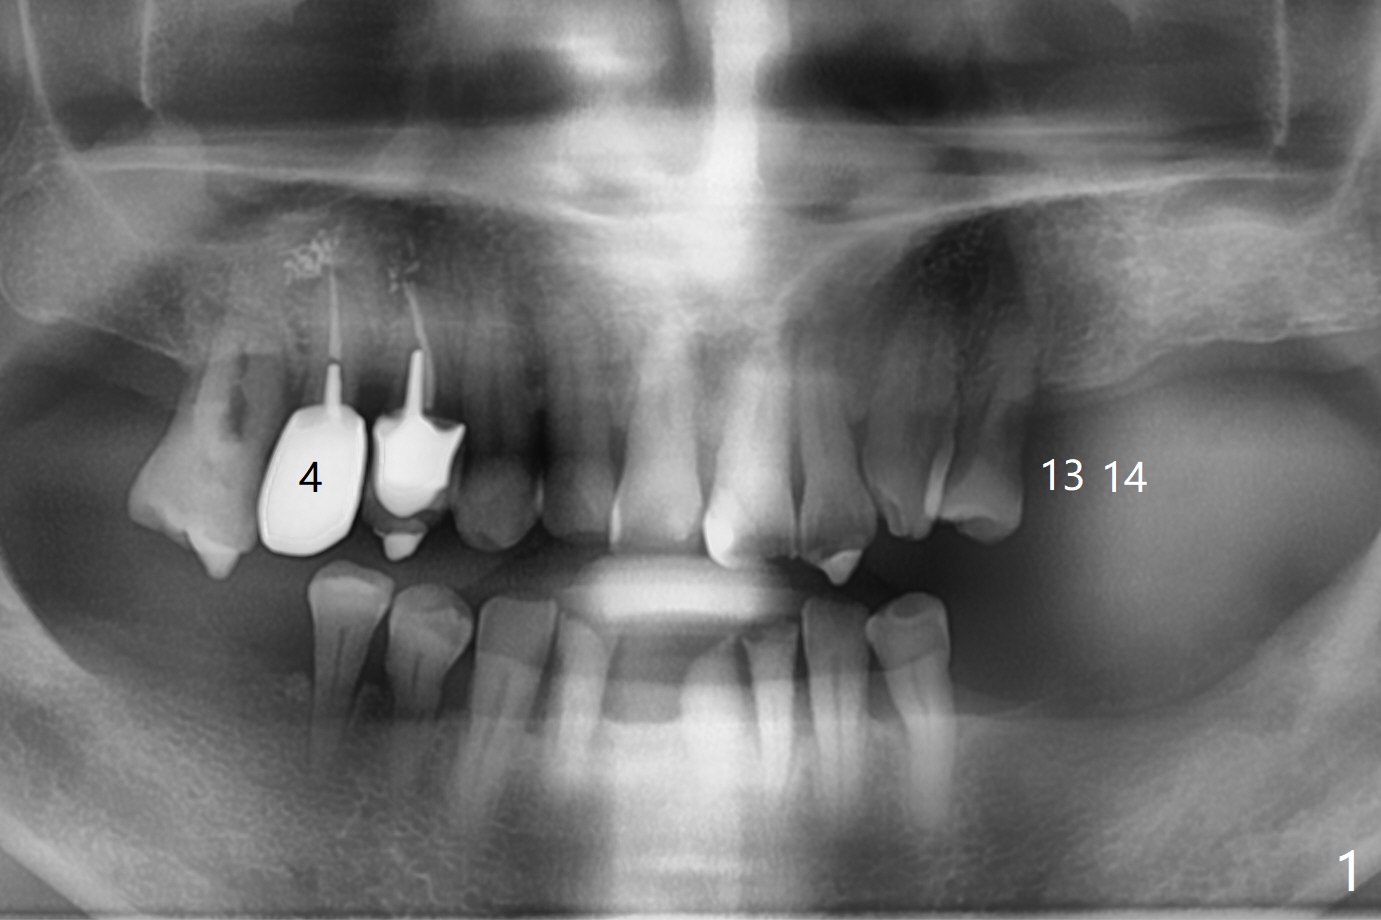

A 66-year-old man has lower RPD. Masti-cation is difficult due to #4 root fracture and #13 and 14 missing (Fig.1). After extraction of #4 with socket antibiotic treatment (Fig.2), finish #13 and 14 osteotomy and implant placement (Fig.3,4). Save auto-genous bone from #13, 14 and #4 using suction trap for #4 buccal gap closure.